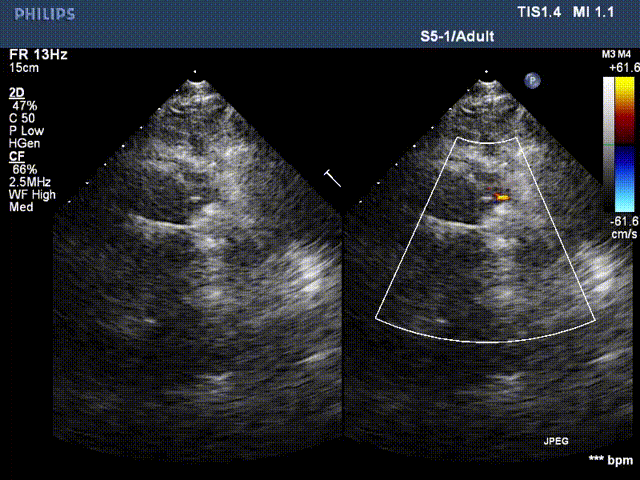

患者李某某,男,61岁,现病史:高血压15年,15年前行主动脉瓣置换术,13年前行升主动脉置换术、冠状动脉旁路移植术。主因心脏瓣膜术后15年,突发胸闷气短20天入院。检查提示:主动脉夹层动脉瘤,主动脉瓣位机械瓣位置、动度未见异常,升主动脉位人工血管上段吻合口漏,原有升主动脉管壁与人工血管之间液区,向右房分流,肺动脉高压(收缩压约51mmHg)。EDV: 192ml, ESV:102ml, FS:23%, SV:89ml。

术中操作